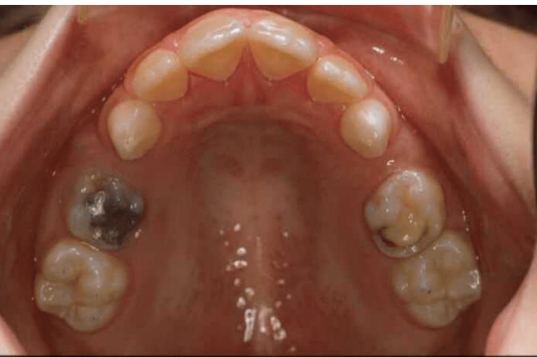

what age is this pt

10/11/12 years

tx option for retained primary teeth on RHS

extraction

in which caries risk category would you place this pt

and why (3)

high risk

existing restorations

new carious lesions

early loss of primary tooth (64)

which radiographs would you take to further investigate caries in posteiror teeth

bitewings

bitewings confim no caries in FPM

what preventative tx would you provide

fissure sealants

which caries risk category

why (3)

high

existing restorations in 85, 84, 74

buccal swelling adjacent to 85

new carious lesion in 75

which 2 teeth have been temporised

85

84

which tooth is erupting distal to the last tooth on patients RHS

46

at what age do 6s usually erupt

6 years

what preventative tx would you provide for 46 when erupted

fissure sealant

5 possible fluoride containing preparations and doses, which would be suitable for this pt who lives in an area with less than 0.3ppm fluoride in drinking water